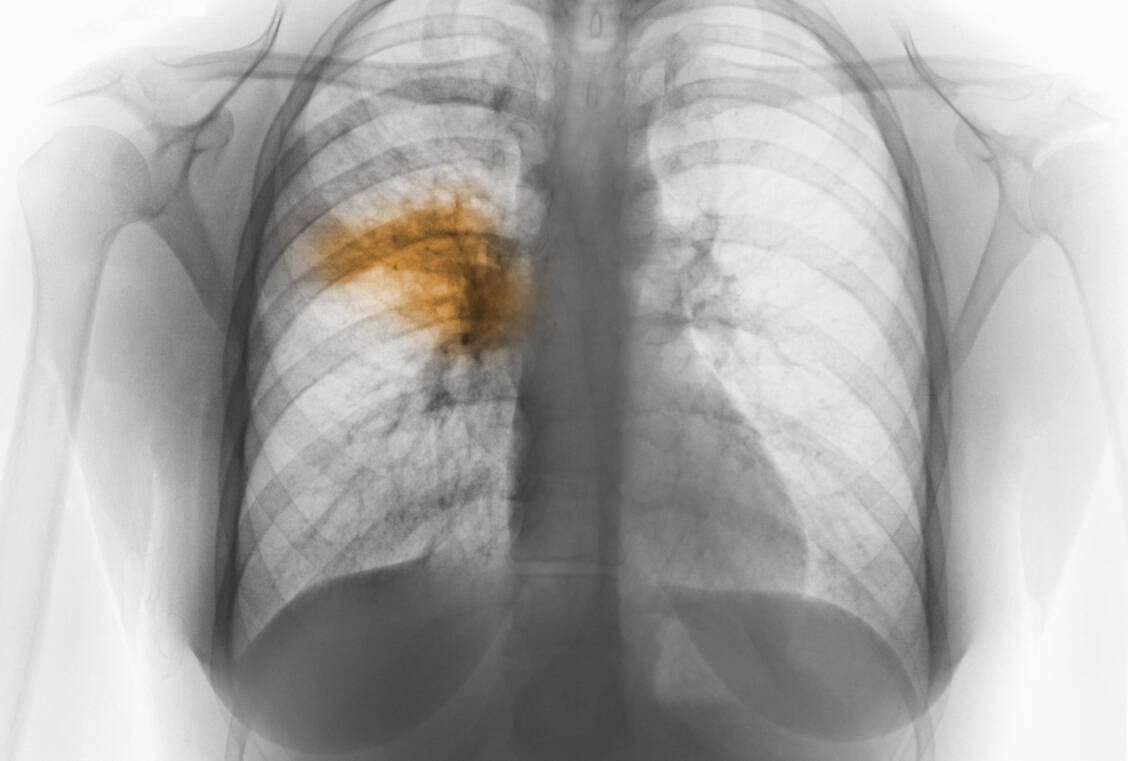

An der in China ausgebrochenen Lungenkrankheit ist ein zweiter Patient gestorben. Wie die Gesundheitskommission der zentralchinesischen Metropole Wuhan mitteilte, starb der 69-jährige Mann bereits am Mittwochmorgen in einem Krankenhaus. Fünf der 41 Patienten, bei denen das neuartige Coronavirus seit Ende Dezember festgestellt worden war, blieben demnach weiterhin in einem kritischen Zustand. Jedoch seien keine neuen Infektionen festgestellt worden. 644 von 763 Menschen, die nach dem Ausbruch unter medizinische Beobachtung gestellt wurden, konnten entlassen werden.

Es wird vermutet, dass das Virus von einem Tiermarkt in der Millionenstadt kommt. Der erste Todesfall war am vergangenen Samstag bekannt geworden. Ein Mann mit schweren anderen gesundheitlichen Problemen war an den Komplikationen gestorben. Nach den Erkrankungen in Wuhan war das Virus diese Woche erstmals im Ausland bestätigt worden. Der Erreger wurde bei einer Chinesin in Thailand und einem Chinesen in Japan nachgewiesen, die zuvor beide in Wuhan waren. Am Freitag bestätigten die Behörden in Thailand eine weiteren Fall. Demnach wurde das Virus auch bei einer 74-jährigen Frau aus China nachgewiesen. In Hongkong, Singapur und Südkorea gibt es ebenfalls Verdachtsfälle, die aber nicht bestätigt sind.

Möglicherweise kommt das Virus aus der Tierwelt. Bislang gibt es laut Weltgesundheitsbehörde WHO «keine klaren Beweise» für eine Übertragung des Virus von Mensch zu Mensch. Medienberichten zufolge handelt es sich um keine neue Virusart, sondern eine neue Variante des SARS-assoziierten Coronovirus. Das Robert Koch-Institut schätzt das Risiko für die Gesundheit der Bevölkerung in Deutschland zurzeit als sehr gering ein.